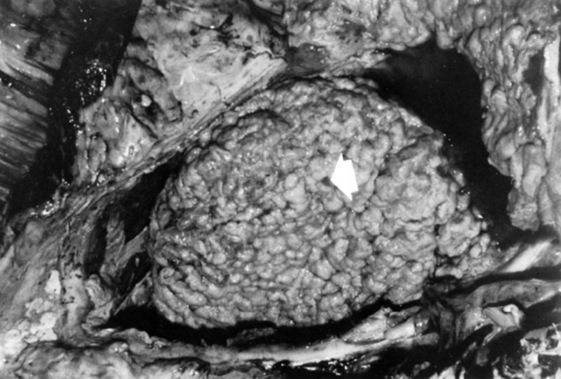

Necropsy Findings

VSD is usually located high in the interventricular septum just ventral to the right or noncoronary cusp of the aortic valve in the left ventricle and underneath the septal leaflet of the tricuspid valve or caudal or ventral to the crista terminalis in the right ventricle. It can be an isolated defect or can be accompanied by other cardiac or organ anomalies. If the defect is moderate or large, there is right ventricular, left atrial, and left ventricular enlargement and pulmonary artery dilation. The lungs may be congested because of increased pulmonary blood flow, and secondary pneumonia is not uncommon. If pulmonary vascular resistance was increased, right ventricular hypertrophy may be present. There may be secondary endocarditis (infrequent in large animals)58 or endocardial lesions as a result of turbulent blood flow across the defect.